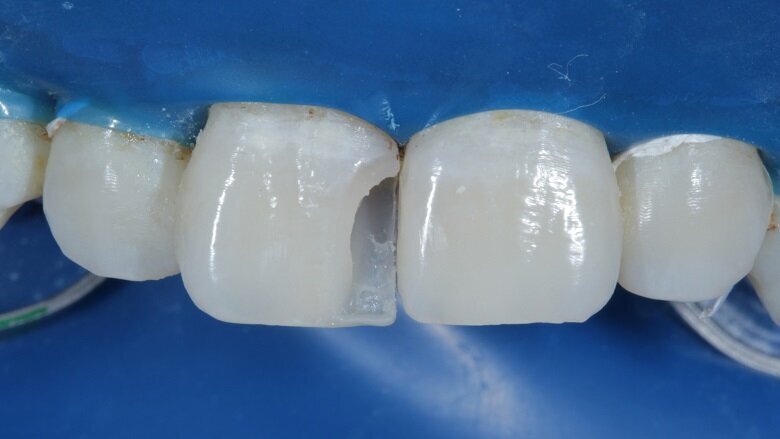

To begin with, the shade (hue) was evaluated using the button technique before isolation. Small balls of different shades of composite (dentin, body and enamel) were placed on the tooth and cured (Fig 4). Value is another important factor which needs to be considered while shade matching.

Fig 4: Shade Evaluation : Button technique (Hue)